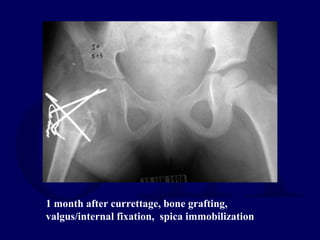

Currettage, biopsy consistent with

aneurysmal bone cyst

1 month after currettage, bone grafting,

valgus/internal fixation, spica immobilization